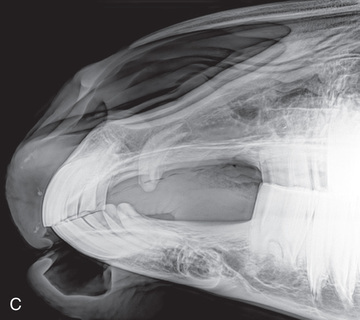

Pelvis, skull, spine, thorax, and abdomen radiographs are completed much like those in horses. In the case of a small calf, radiographs may be performed in the clinic with use of positioning and techniques similar to those used for a large dog. A mobile x-ray machine can be used to take thoracic or abdominal radiographs in a small calf (Fig. 24.62).

Small ruminant patients (sheep/goats) and swine can be radiographed much like small animals (Fig. 24.63). Because they can be easily transported, small ruminant patients are often radiographed within the clinic setting.